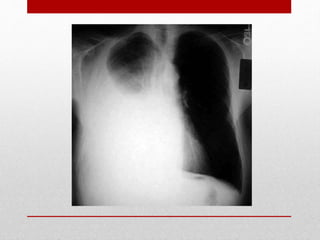

DIAGNÓSTICO

RADIOLOGICO

RADIOGRAFIA DE

TÓRAX

• Es el estudio más valioso en la evaluación del trauma

• Se realiza en condicione sub-óptimas

• Valorar:

• Hemotórax

• Neumotórax

• Infiltrados pulmonares

• Posición de TET (si se intubó)

• Ensanchamiento o desplazamiento mediastinal

• Situación de los diafragmas

• Lesiones esqueléticas